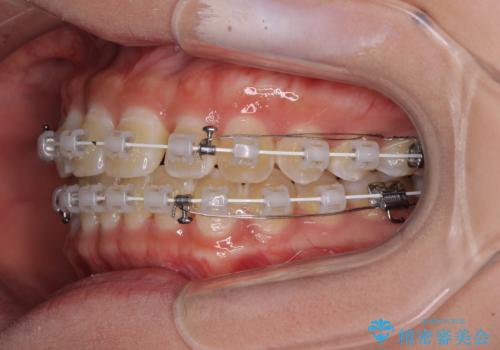

- 矯正装置

- 審美装置

- 上下前歯隙間と正中のズレを改善したいとのことで来院された患者様です。

自己管理を減らしたいとのことで、ワイヤー装置による矯正治療を行うこととしました。

正中がなかなか合わずに、2年近くの治療期間を要しました。